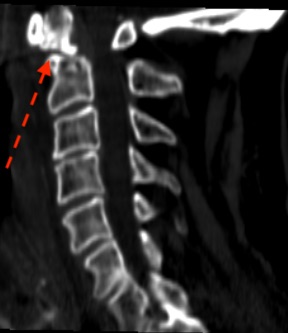

La reconstrucción sagital puede inducir a error al creer que la fractura (flecha verde) puede tratarse de manera conservadora ( tipo I)

Sin embargo, la reconstrucción coronal del mismo paciente nos indica claramente que la fractura (flecha roja) se ubica en la base de la odontoides